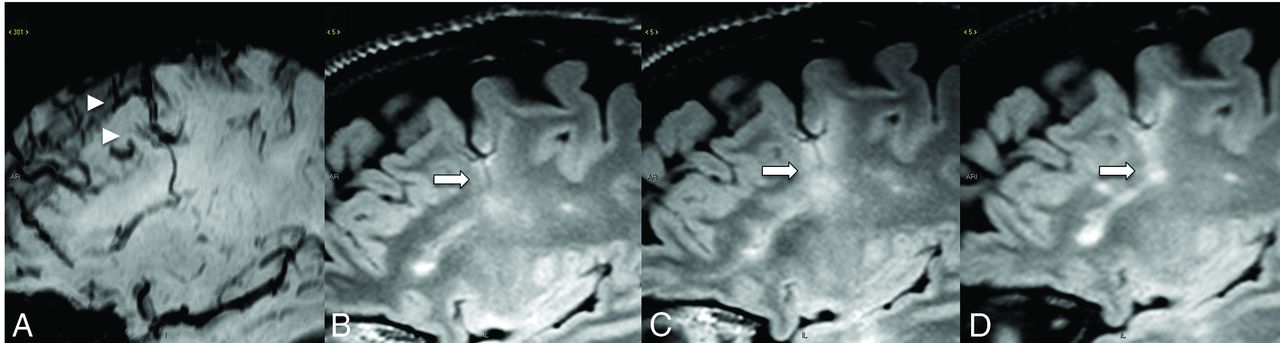

FLAIR (A) shows a mixed-signal-intensity CCM (arrowhead) in the left insular cortex with an internal blood-fluid level and no perilesional edema. A collector vein of a DVA (arrow) is seen from the ventricular ependyma to the CCM, which is barely visible on the SWI (B) and becomes more conspicuous on the susceptibility-weighted MIP image (C).